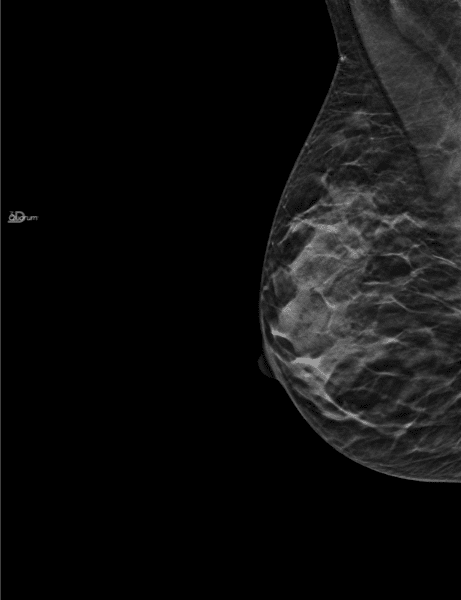

Routine examination, with no palpable mass on clinical examination.

The mammogram, as interpreted by the radiologist, was followed by an ultrasound due to dense breasts. During this scan, a 0.81 cm diameter ACR4-classified mass was detected in the upper-external quadrant of the right breast. The biopsy revealed an infiltrating canal cancer.

A second reading of the mammogram with MammoScreen located the cancerous area as a mass on the right side, which scored a 7 on the MammoScreen Score. This case shows the interest of AI in the detection of small subtle cancers that may not be detected by the radiologist for different reasons (fatigue, delay, distraction by other tasks…).

Fortunately the cancer was caught in this case by ultrasound for dense breasts, but the systematic reading with AI assistance would allow with certainty to suspect the cancer and make an oriented ultrasound.